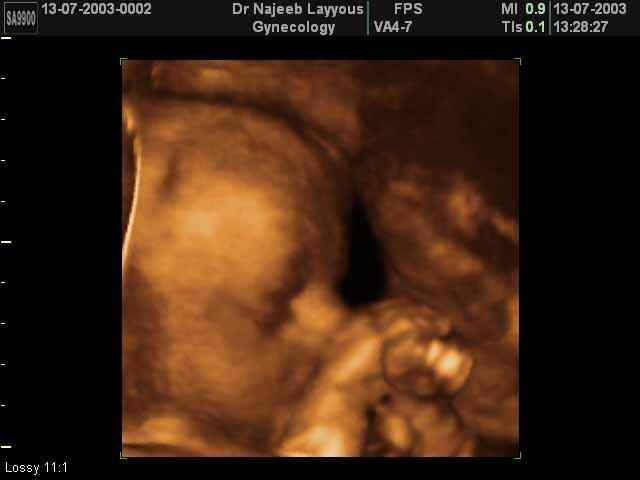

- صور لوجه الجنين في داخل الرحم

- صور جانبية لرأس الجنين